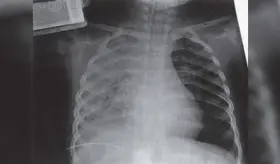

Radiólogo especialista destaca la importancia de la visión independiente del profesional en imágenes diagnósticas para detectar fibrosis pulmonar progresiva y guiar tratamientos específicos según cada patología autoinmune.